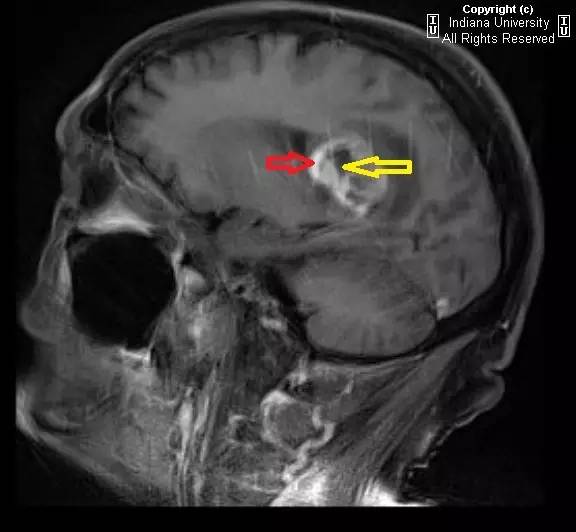

图 4 增强 MR 矢状位,病灶成周边强化(红色箭头),中央低信号表明有坏死性改变(黄色箭头)

可见一中心位于胼胝体压部的占位性病变,密度不均,中心为低密度,周围环状水肿。推压双侧脑室。右侧侧脑室室管膜极有可能受累。占位蔓延进入双侧半卵圆中心,右侧明显。MR 上,病灶成周边强化,中央无强化低信号表明有坏死性改变。

影像学上表现为厚壁、不规则、周边强化的肿瘤组织包绕中央坏死区。可见占位效应和瘤周水肿\肿瘤浸润。出血少见。肿瘤范围远大于 MR 上异常信号范围。